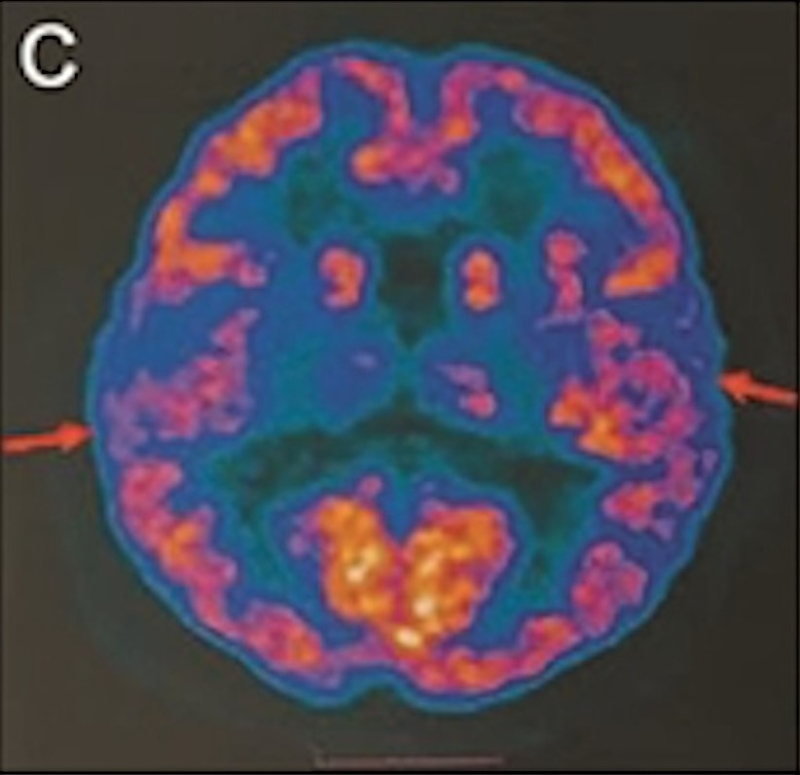

最年轻的19岁阿兹海默症男子脑部扫描结果:

▲19岁阿兹海默症(认知障碍症/脑退化症)男子脑部扫描结果。北京青年报

该名19岁男子到医院接受多项检查,包括脑脊液指标检测及正电子扫描。结果显示,他出现轻度脑萎缩等症状,最终被临床诊断为“阿兹海默症”。